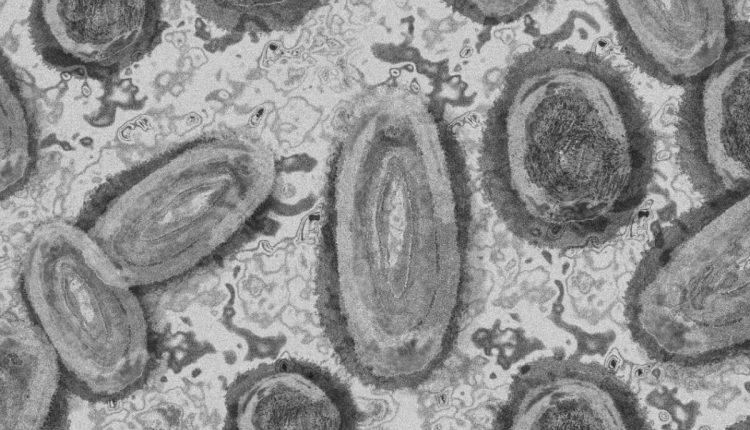

A varíola causada pelo vírus hMPXV (Human Monkeypox Virus, na sigla em inglês) causa uma doença mais branda do que a varíola smallpox, que foi erradicada na década de 1980.